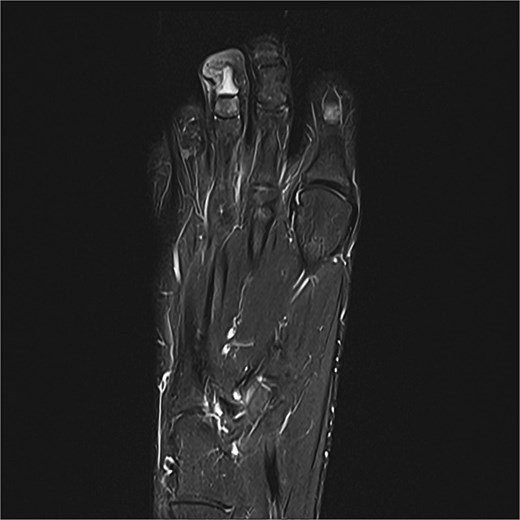

Preoperative MRI from case 2 demonstrating SE and associated bone marrow edema.

A 14-year-old female presented with recurrent SE of the right great toe (Fig. 4). She had a history of osteomyelitis in the same location, treated successfully before SE developed. MRI confirmed recurrence with underlying osteomyelitis (Fig. 6). Surgery was performed 2 days later (Fig. 5). Bone cultures revealed Staphylococcus sciuri, Staphylococcus caprae, and Staphylococcus warneri, with sparse growth in all five samples. She transitioned to oral dicloxacillin after 1 week of intravenous therapy. At 16 days, she was asymptomatic, and a 3-month follow-up was scheduled.